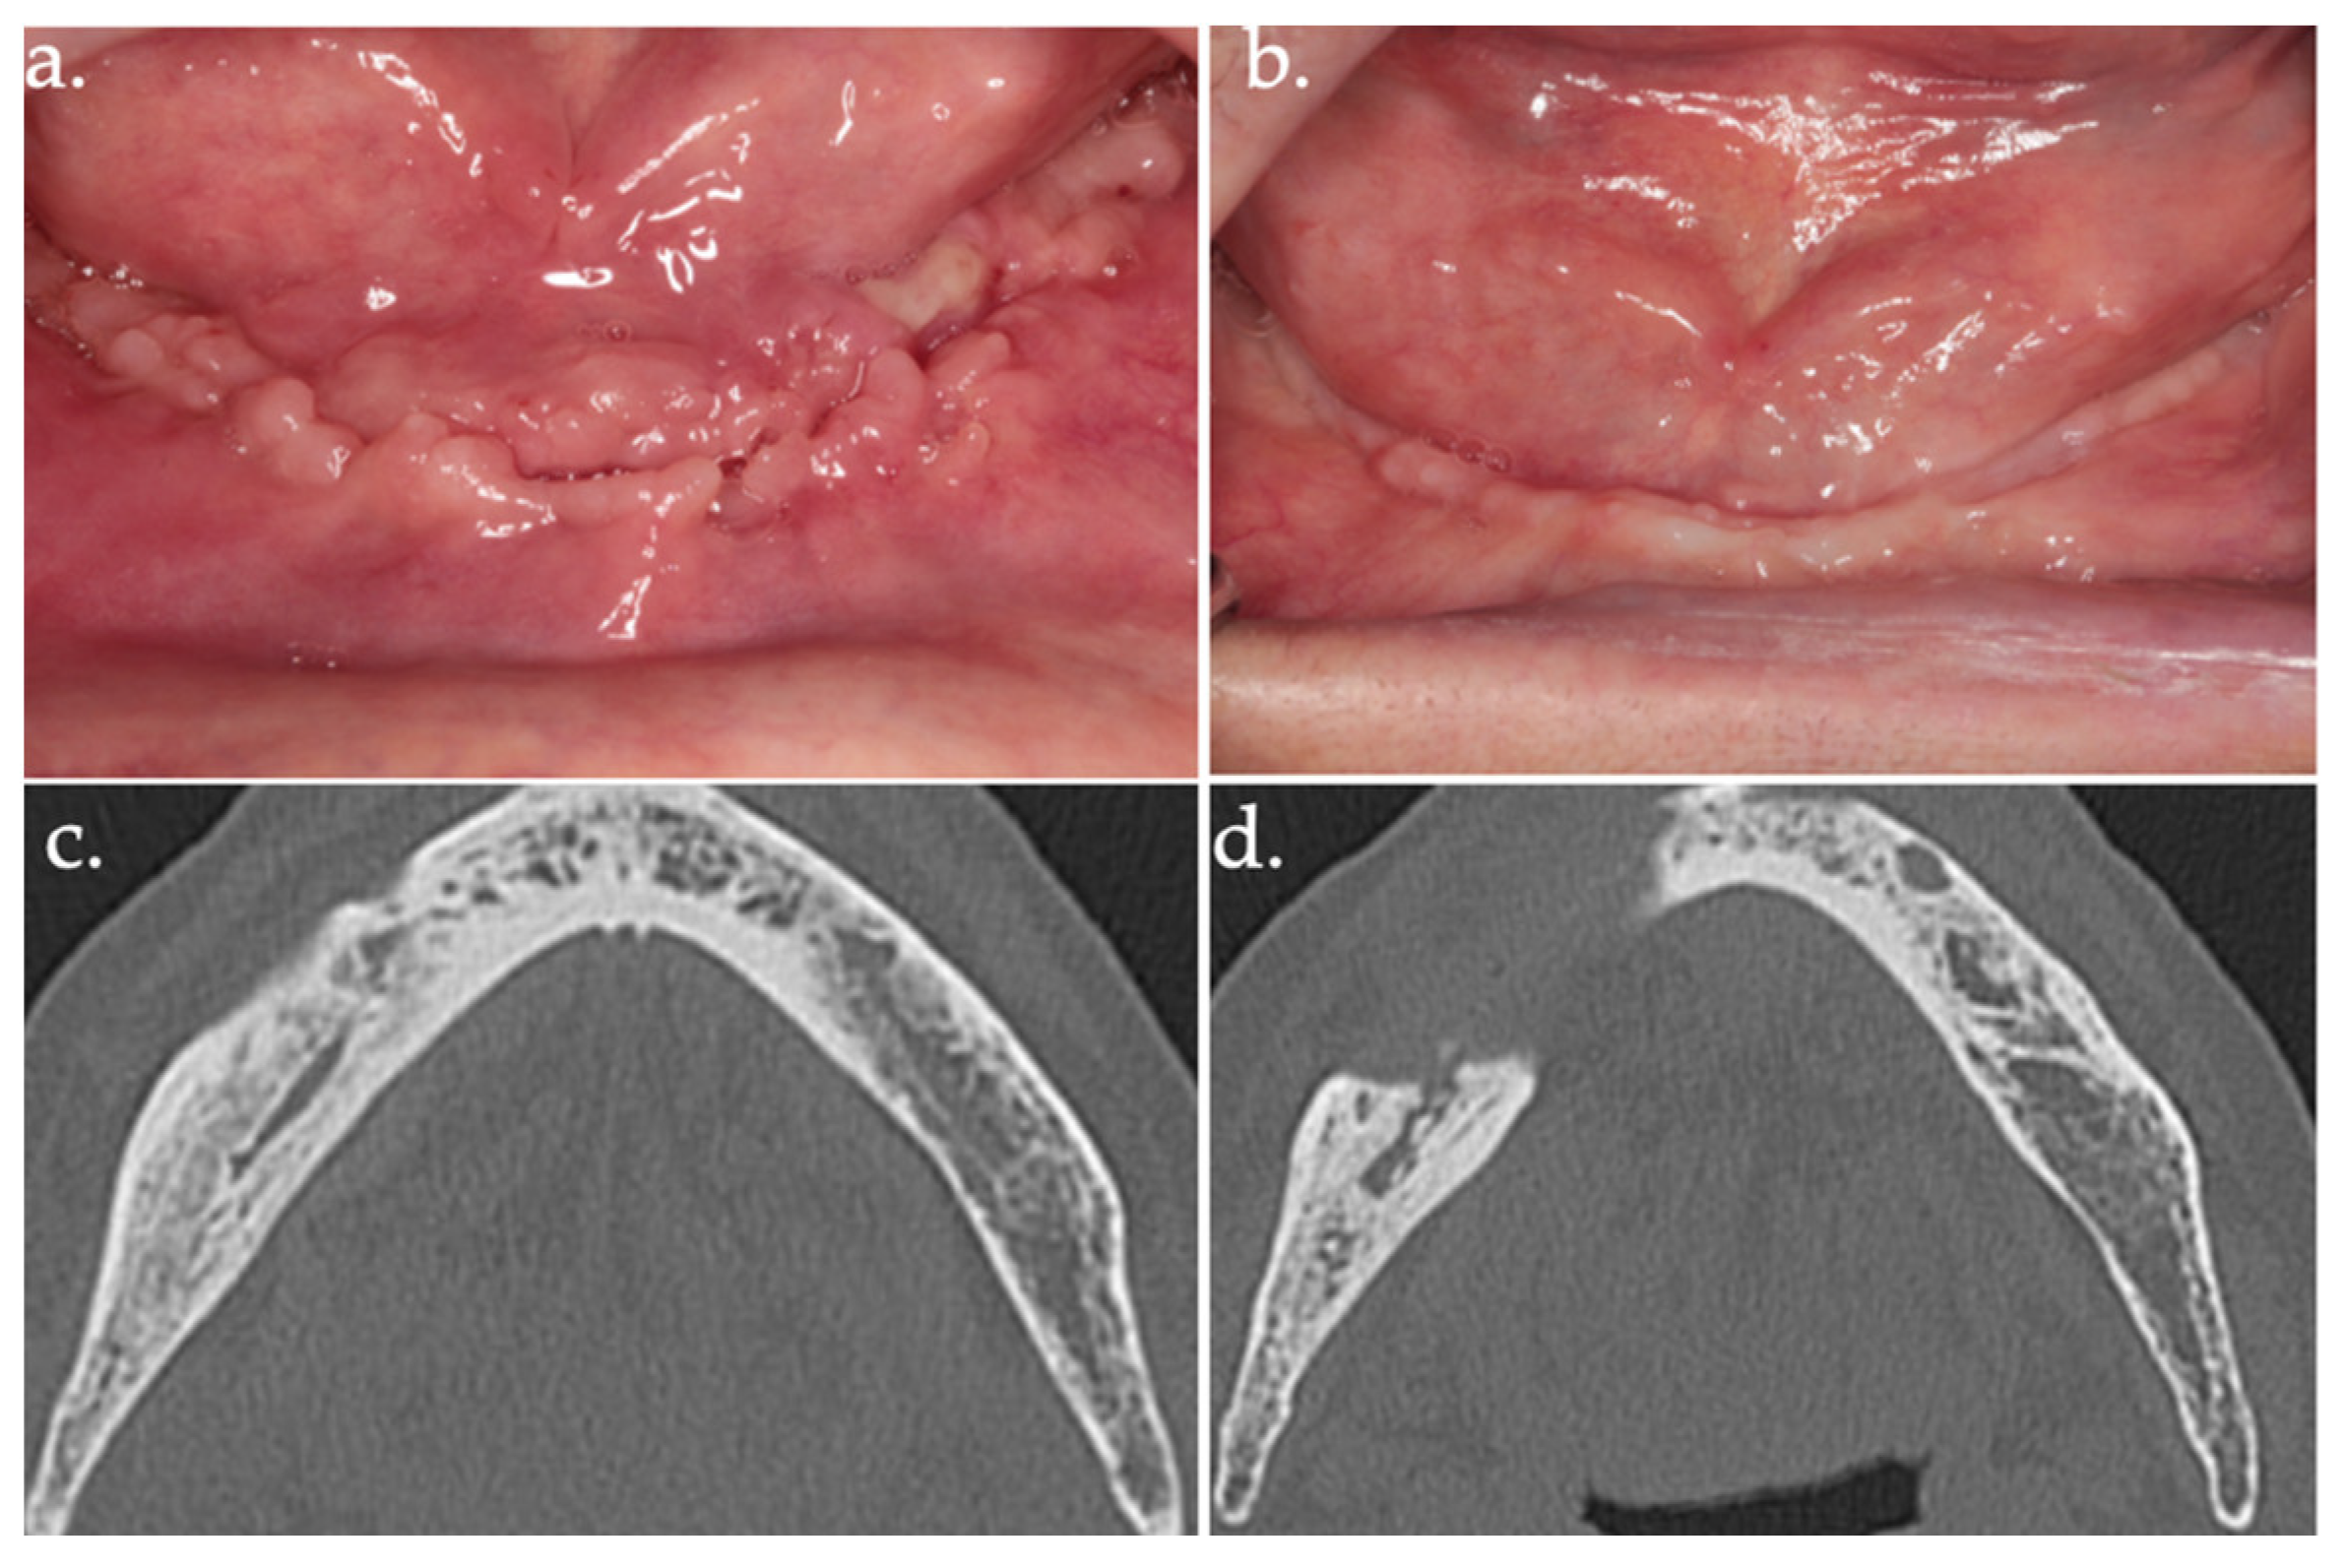

Figure 7.

24 days follow-up (a); 17 months follow-up (b); follow-up CT scan at 18 months after surgery (c,d).